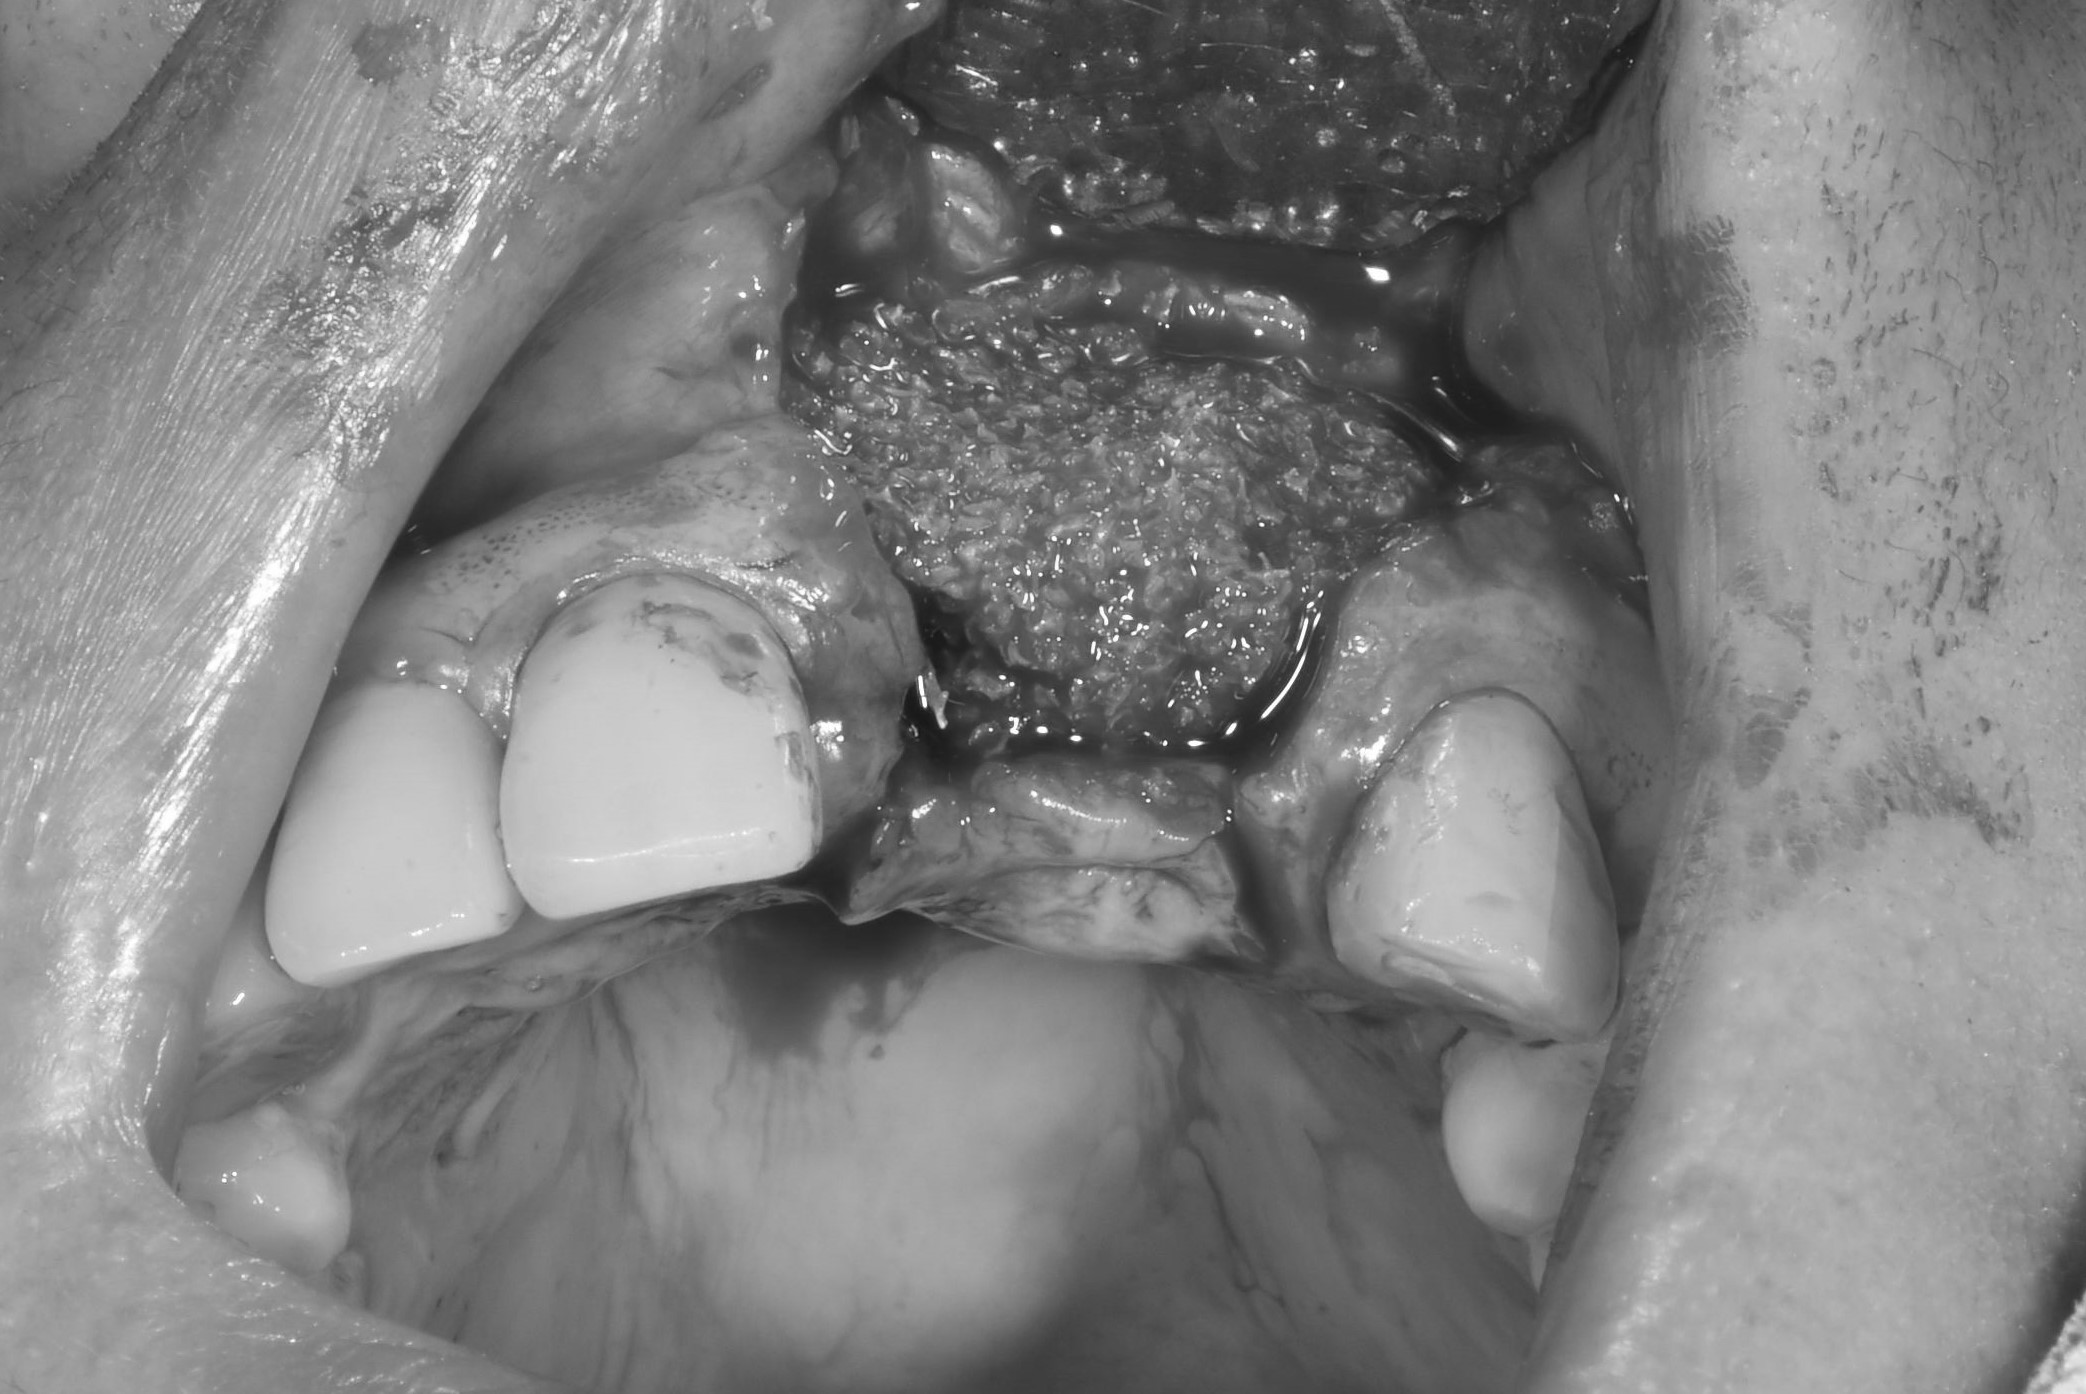

案例三

缺牙太久造成齒槽骨大量流失

先放入不可吸收骨膜,增加骨頭高度與面積